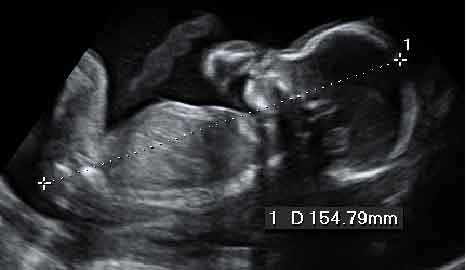

La imagen de la ecografía en 4D ha captado a este feto de 19 semanas de gestación moviendo sin parar sus brazos y piernas. Sus extremidades inferiores y superiores ya tienen una longitud acorde al resto de su cuerpo.

En este vídeo podemos apreciar a un bebé de 19 semanas con todos los miembros en activo, imágenes muy apreciadas por los especialistas. Junto al movimiento de brazos y piernas, se aprecia perfectamente el cordón umbilical.